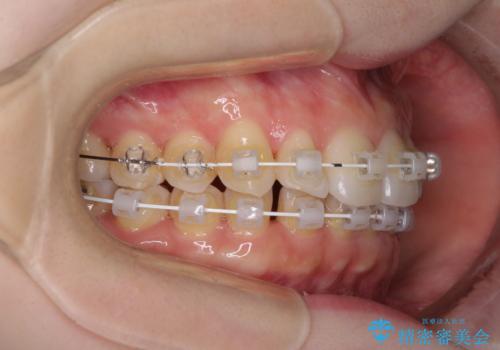

- 矯正装置

- 審美装置

半年もせずにインビザラインを全く使用することができなくなってしまったので、治療開始から1年ほどでワイヤー矯正へ変更することとなりました。

ワイヤー矯正へ変更してからはあっという間に治療が進み、1年弱で終えることができました。